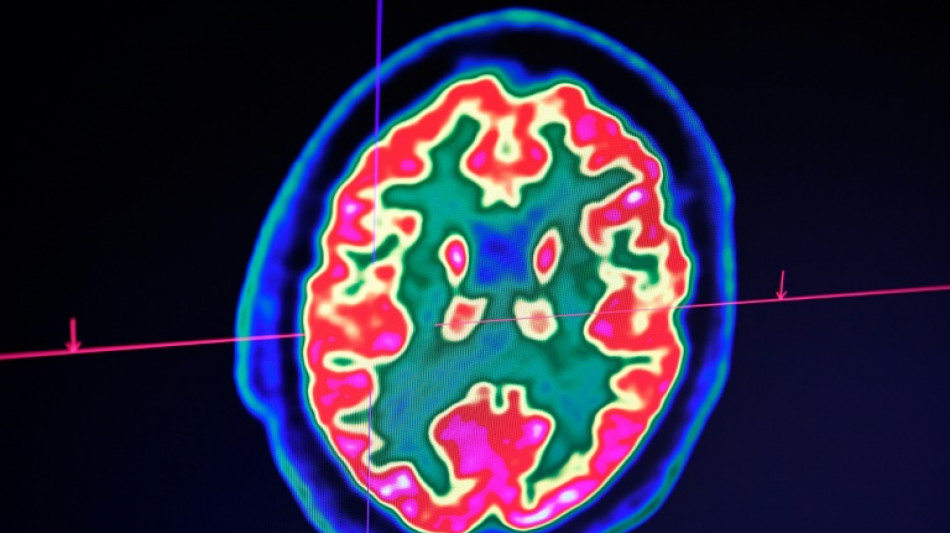

Rare mais fatal, le gliome infiltrant du tronc cérébral est l'une des formes les plus redoutables des cancers du cerveau pédiatriques. Un enfant, pourtant, semble défier les statistiques: sa guérison, unique au monde, suscite aujourd'hui de grands espoirs pour la recherche.

Inopérable, ce cancer est traité habituellement par une radiothérapie, qui permet parfois de freiner la maladie mais dont l'effet est transitoire. Aucun médicament n'a encore démontré son efficacité.

D'emblée, Lucas répond très bien au traitement. "Au fil des IRM, j'ai vu la tumeur complètement disparaître", raconte le Dr Grill, qui n'ose, malgré ces résultats miraculeux, décider d'arrêter le médicament. Jusqu'à ce qu'il comprenne, il y a un an et demi, que l'enfant avait lui-même cessé de le prendre.